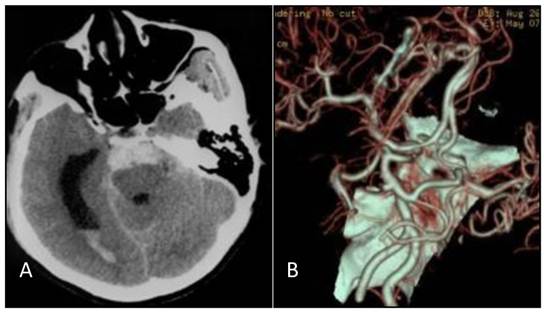

Figure 1

A: Head CT scan shows that the hemorrhage was localized on the pontine cistern and interpeduncular cistern, extending to the right of the ambient cistern, into the posterior horn of the right ventricle. The patient was diagnosed with subarachnoid hemorrhage (SAH). B: Head CT angiograph shows mound-like protuberances at the apex of the basilar artery with a diameter of 3.2 mm, no signal at the bilateral internal carotid artery, and bilateral posterior communicating artery supplying the circulation.